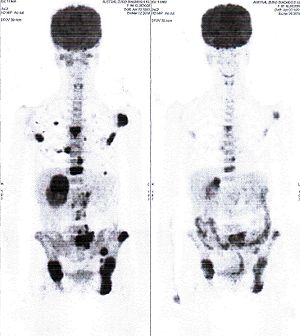

Below are some of the cases, from more than 80 cases we have treated so far with good results. When reading the PET/CT scans, the picture on the left is before treatment, and the picture on the right is after treatment. The intensity of black represents the activity of the cancer, but some black areas are not cancer: brain, heart, radioactive urine in bladder. For the heart, the intensity of black depends on the number of hours of fasting: if more than 10 hours, the heart is not even black, but if fasting is less than 6 hours, it is very black. The intensity of black in the brain can be variable in different scans depending on the brain activity at the time of the scan. The intensity of black in the radioactive urine can also be variable due to the hydration of patients and the time of injection of diuretic.

CASE NO: 1

(HEPATOCELLULAR CARCINOMA + STOMACH CANCER)

A middle-aged women who is very thin and very weak, can hardly walk, lying in bed most of the time. She saw a cancer specialist in a top hospital who discovered that she had massive hepatocellular carcinoma, and another cancer in the stomach. Given that hepatocellular carcinoma is incurable and stomach cancer is very difficult if not impossible to cure without surgery, she was told that nothing could be done for her. She came to ask us to help her. After just 4 treatment, the hepatocellular carcinoma went into remission, and the stomach cancer (arrow) became less active. Until today, more than 6 months later, the hepatocellular carcinoma is still in remission.

CASE NO: 1 - A FEW MONTHS LATER

A few months after successful treatment for hepatocellular carcinoma, and partially successful for stomach cancer, the PET/CT scan showed the stomach cancer becoming very active, with several metastases to the parts of the liver not previously involved by hepatocellular carcinoma. After a few treatment, all the active stomach cancer lesions in the stomach and in the liver went into remission.